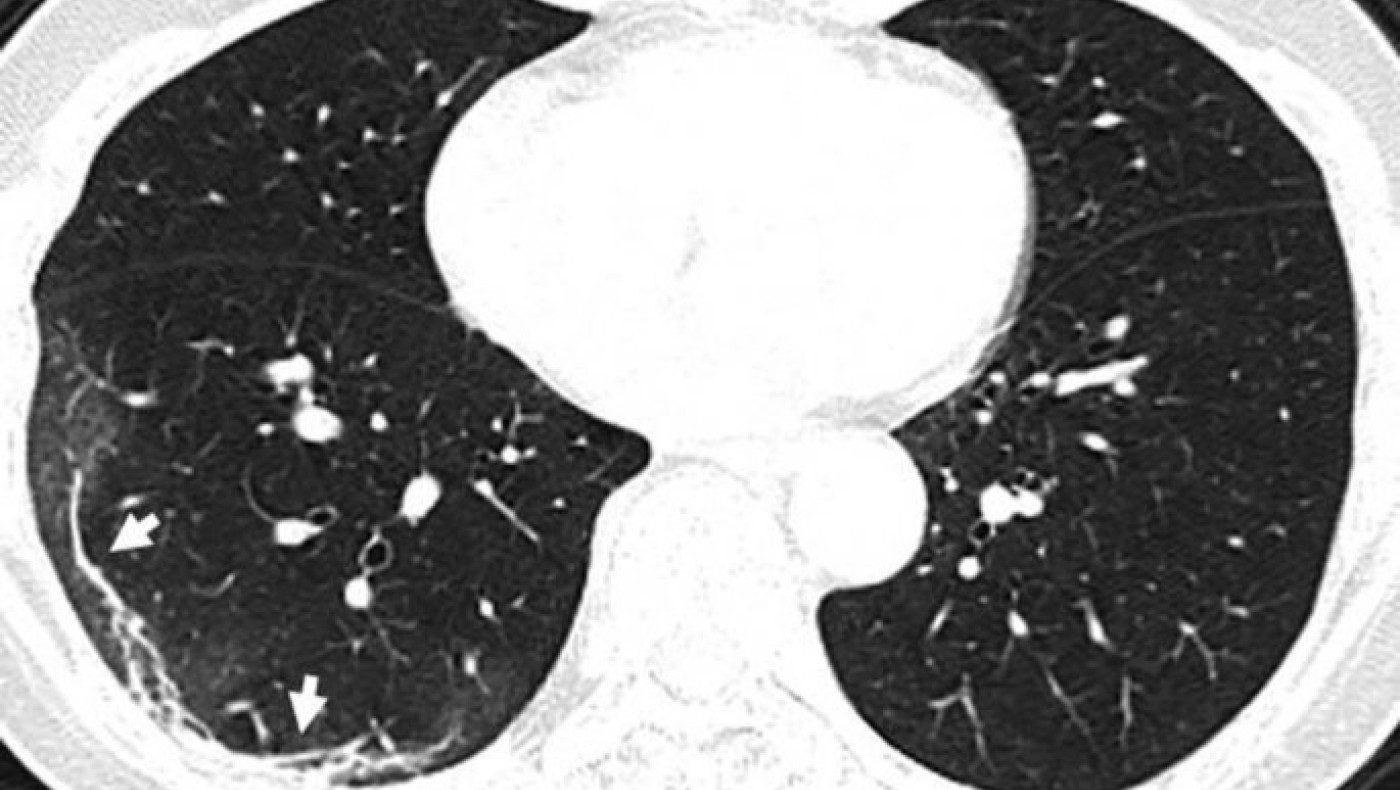

Η πανδημία του κορωνοϊού covid-19 συνεχίζει να καλπάζει σε όλο τον πλανήτη, με τους γιατρούς να παρακολουθούν την έξαρσή του. Περισσότεροι από 4.000 άνθρωποι έχουν χάσει τις ζωές τους από τις επιπλοκές του ιού, ο οποίος προκαλεί σοβαρό πρόβλημα στους πνεύμονες των ασθενών. Στην δημοσιότητα δόθηκαν από την Ραδιολογική Κοινότητα της Βορείου Αμερικής ακτινογραφία πνευμόνων ασθενών, οι οποίοι είχαν προσβληθεί από τον κορωνοϊό, οι οποίες προκαλούν ανατριχίλα.

Οι ασθενείς που έχουν νοσήσει μέχρι στιγμής έχουν περιγράψει την εμπειρία τους ως μια «τρομακτική προσπάθεια για να αναπνεύσουν». Στις ακτινογραφίες διακρίνονται κάποια άσπρα σημάδια, χαμηλά στους πνεύμονες. Περιγράφονται ως υγρό στις κυψέλες του πνεύμονα. Να σημειώσουμε πως οι ακτινογραφίες αυτές που δόθηκαν στην δημοσιότητα είναι από ασθενείς από την Κίνα που νόσησαν με επιπλοκές, οπότε δεν έχουν καμία σχέση με το αν νοσήσει κάποιος ο οποίος δεν αντιμετωπίζει προβλήματα υγείας.